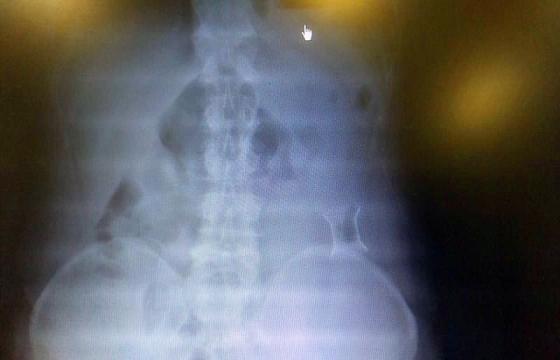

受試患者在結腸端端吻合術中,使用我司新研制產(chǎn)品達到了理想的預期效果。患者術后7天、14X光片顯影,可降解腸道支架均能按研制設計的預期時間節(jié)點保持應有強度,術后21X光片顯示可降解腸道支架已完全破碎,并排出體外。在整個試驗過程中,病患無任何不良反映,耐受良好。